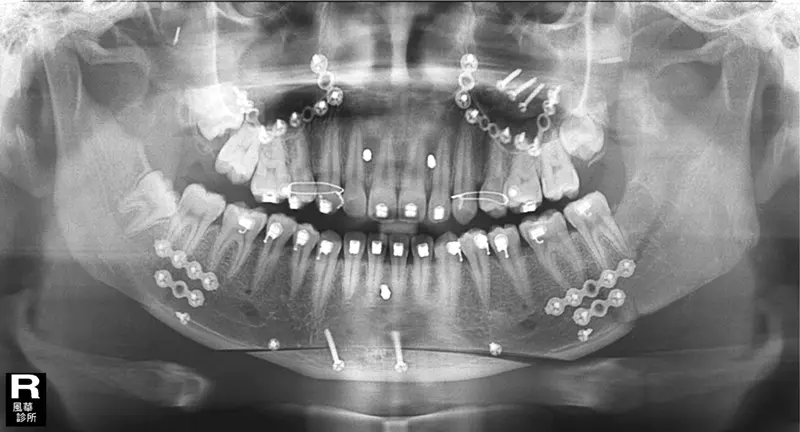

這是我手術完第一次回去拍的X光片,自己張開嘴看不出來,透過X光片才發現原來自己嘴巴一堆骨釘還有骨板,真的滿酷的。 那時候嘴巴都是麻麻的,沒有太多感覺。